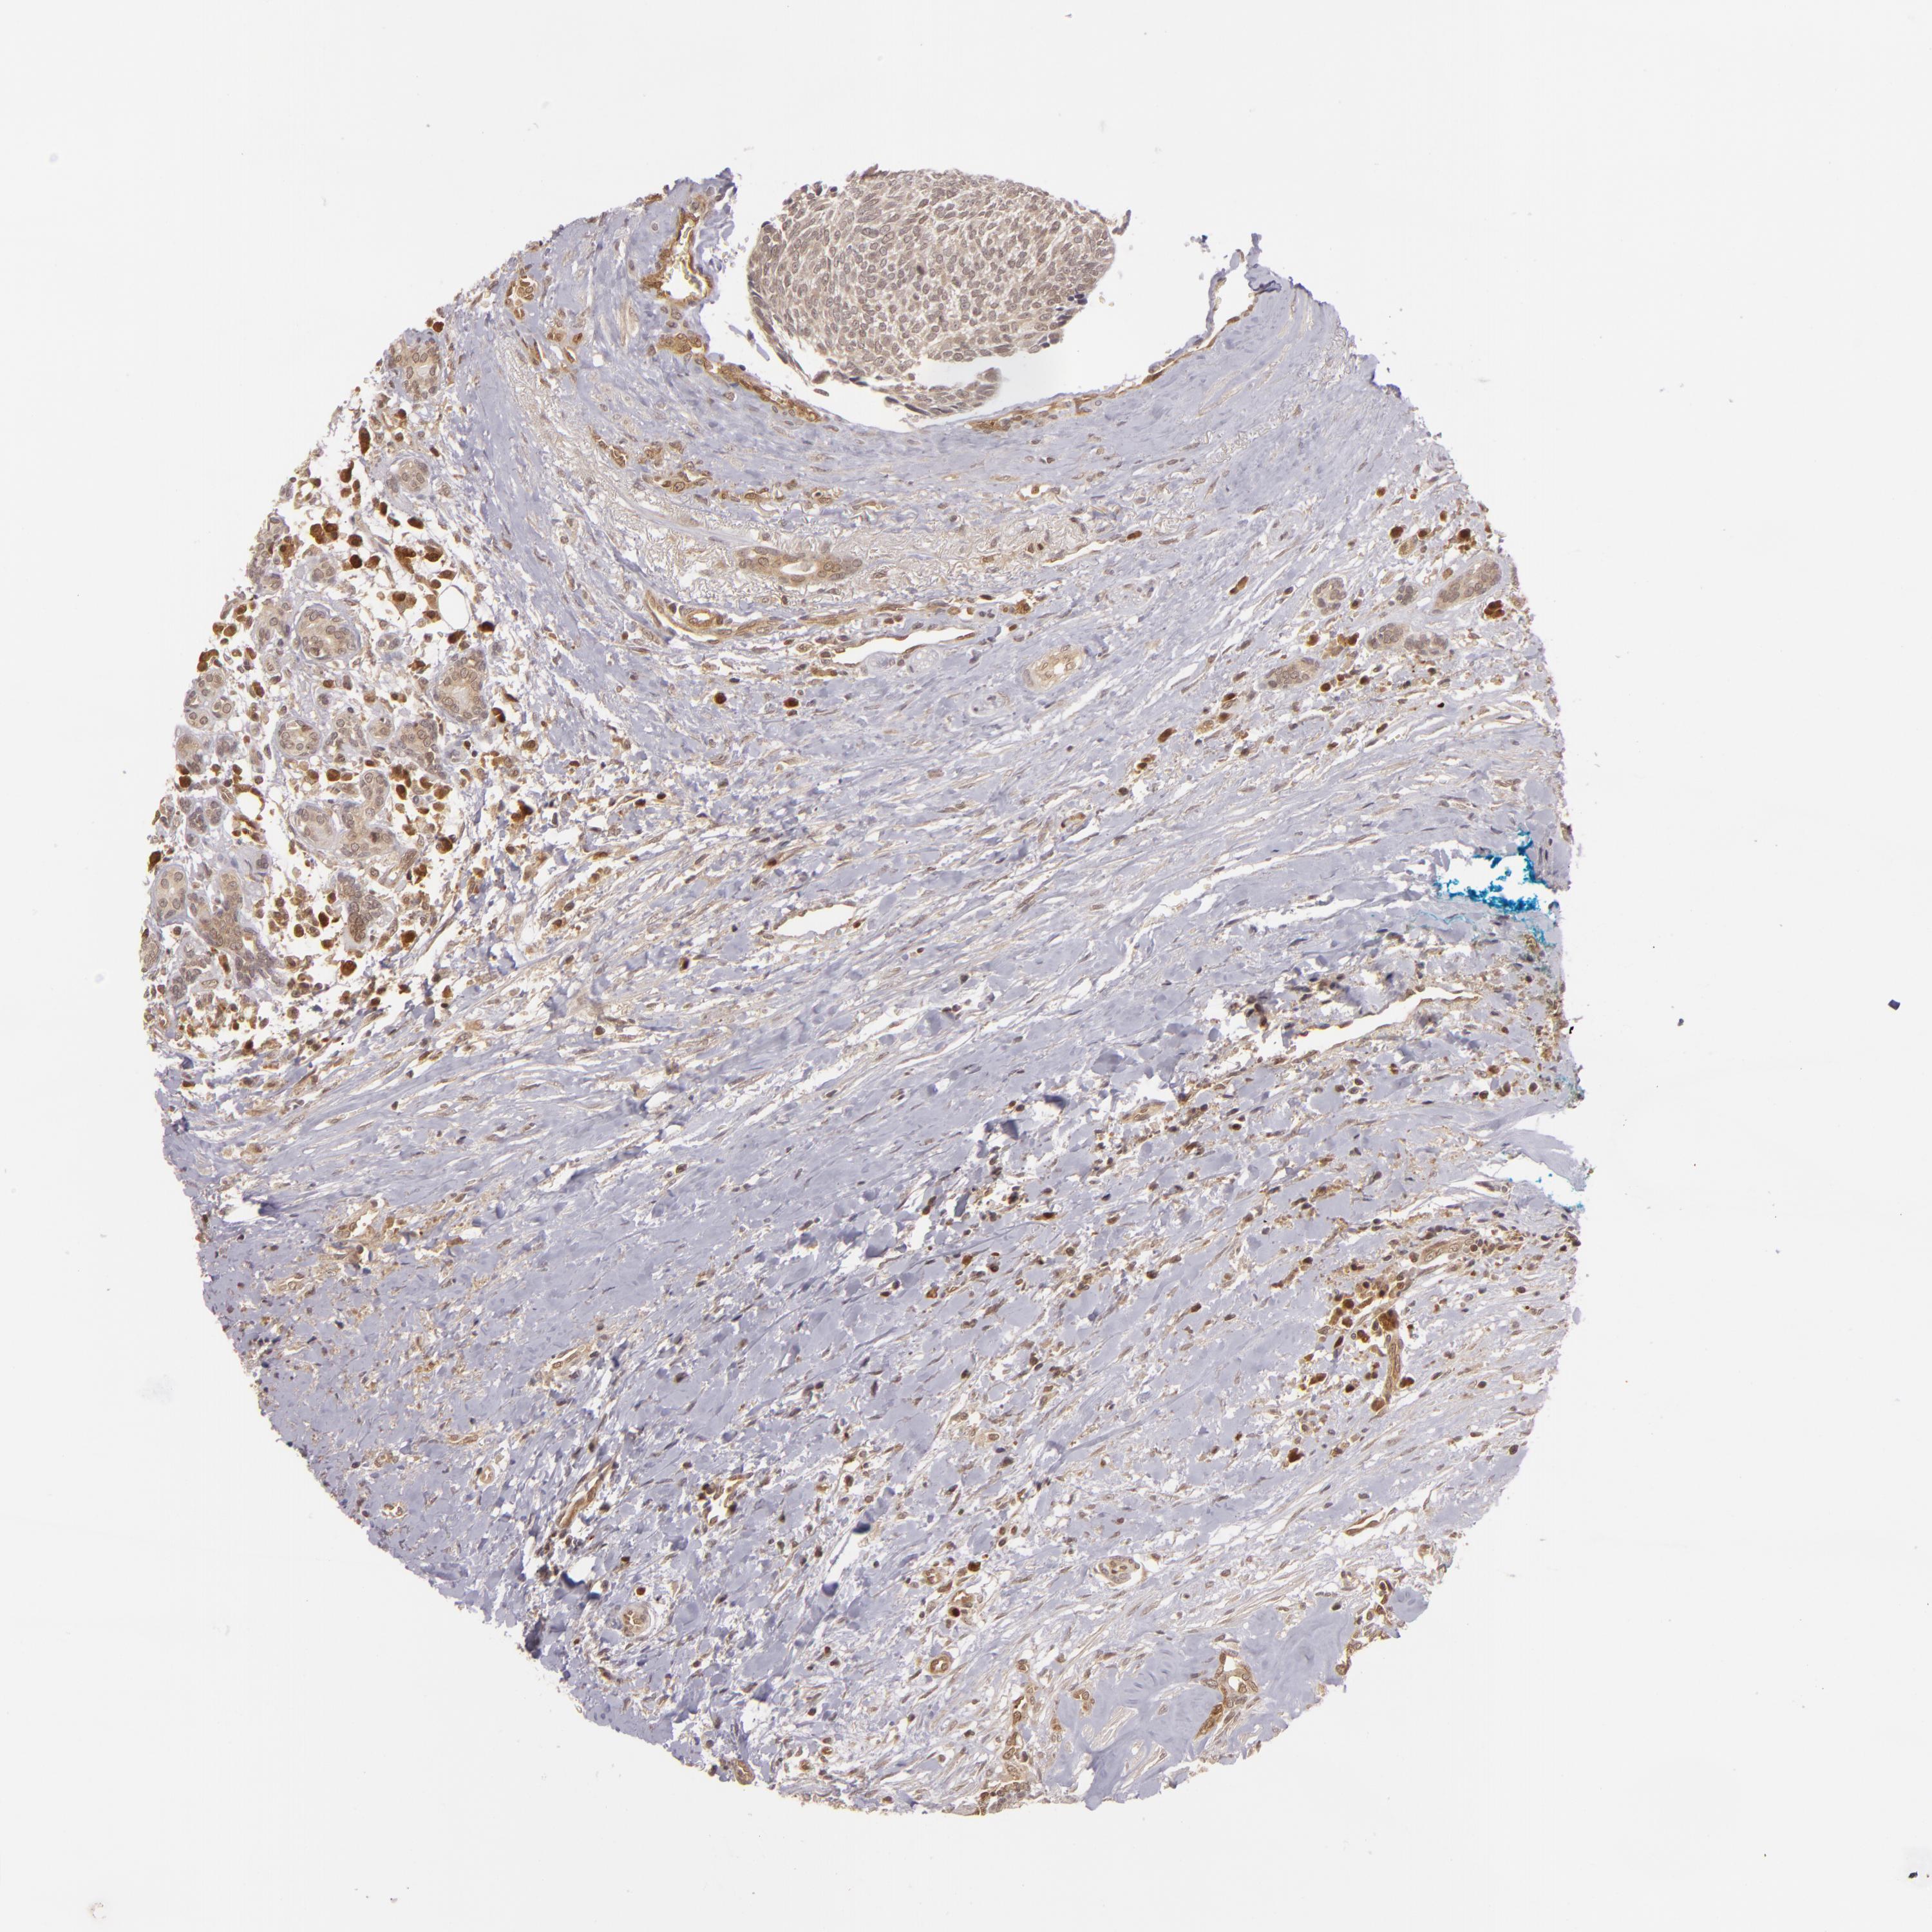

HEAD AND NECK CANCER - Protein expressioni

A mouse-over function shows sample information and annotation data. Click on an image to view it in a full screen mode. Samples can be filtered based on level of antibody staining by selecting one or several of the following categories: high, medium, low and not detected. The assay and annotation is described here.

Antibody stainingi

Antibody staining in the annotated cell types in the current human tissue is reported as not detected, low, medium, or high, based on conventional immunohistochemistry profiling in selected tissues. This score is based on the combination of the staining intensity and fraction of stained cells.

Each image is clickable and will lead to virtual microscopy that enables deeper exploration of all samples and also displays staining intensity scores, fraction scores and subcellular localization as well as patient and tissue information for each sample.

Antibody HPA000755

Squamous cell carcinoma, NOS